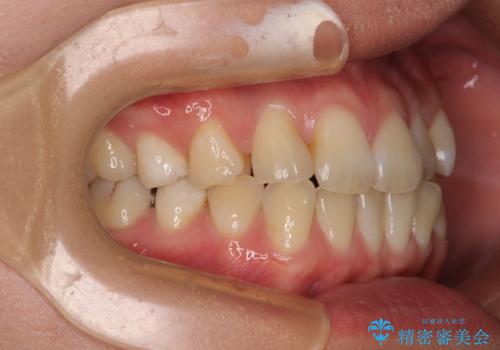

上下前歯のデコボコを気にして来院された患者様です。

ワイヤー矯正でもマウスピース矯正でも可能でしたが、短期間で、自身の手を煩わせることなく治療を行いたいとのことで、ワイヤー装置にて矯正治療を行うこととしました。